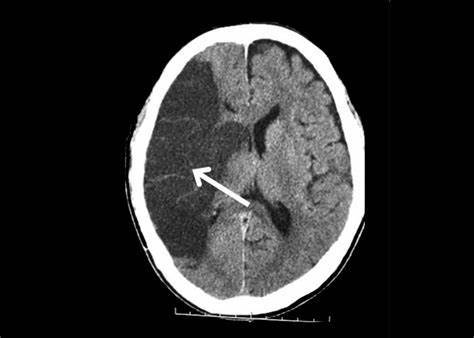

经过医生的检查 , 最后确诊是脑梗死 , 不过梗死的情况不严重 , 及时进行溶栓患者 , 现在已经好多了 。

因为大脑组织缺血出现的坏死 , 我们称为脑梗死 , 其实也叫做缺血性脑卒中 。

如果血管破了 , 血液流出来了 , 这种情况我们称之为出血性脑卒中 。

在所有患者当中 , 脑梗死占有很大比例 , 70%~80%的脑卒中都是缺血性脑卒中 。